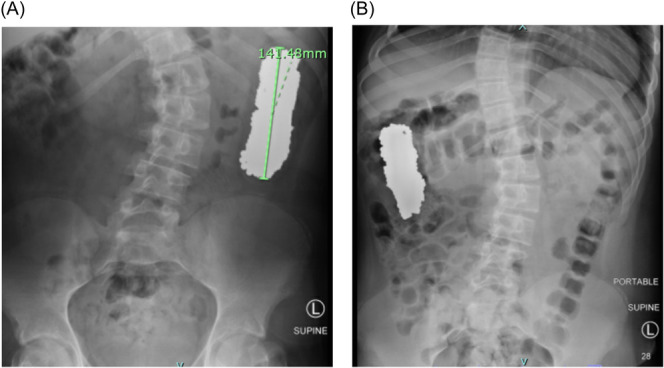

Multiple magnet ingestion warrants appropriate and timely management to avoid serious complications. We report a case of a 14-year-old male with multiple magnet ingestion. Serial abdominal X-rays with misinterpreted foreign body location delayed appropriate management.